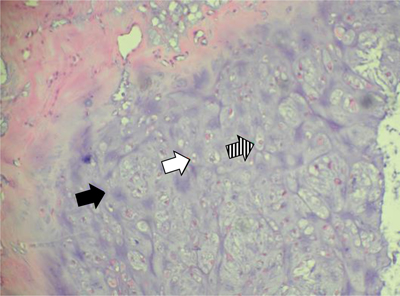

Figure 9

Case 2 – Histopathology of the resected specimen. Hematoxylin eosin staining, 200×: cartilaginous tissue with moderate cellularity. Note chondroid matrix (black arrow) with interspersed small (white arrow) to medium sized (dashed arrow) chondrocytes with no atypia or mitotic activity. There is absence of necrosis.